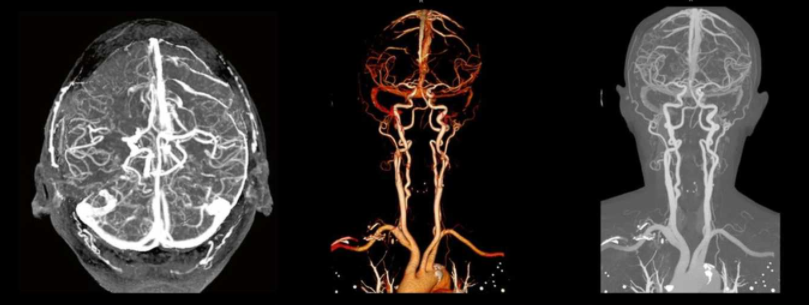

四、“广”——一站式全身血管评估,应用范围广泛

除了在冠心病诊断中的核心应用,双源CT的强大功能远不止于此。它可以进行头颈、胸腹、四肢等全身各部位的血管成像,实现对“泛血管疾病”的一站式评估。无论是主动脉夹层、肺动脉栓塞等致命急症的快速诊断,还是脑血管、肾动脉、下肢动脉等病变的精细评估,双源CT都能提供全面、可靠的影像信息,为临床决策赢得宝贵时间。